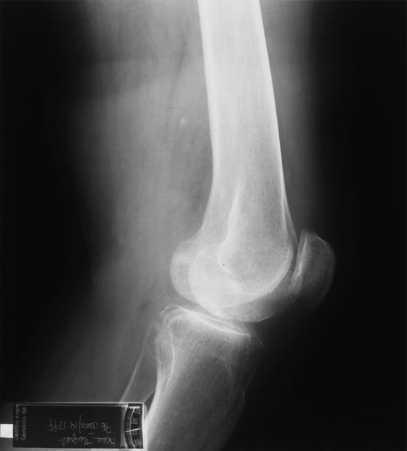

En la exploración radiológica se observan signos indicativos de derrame articular y osteonecrosis del cóndilo femoral interno.